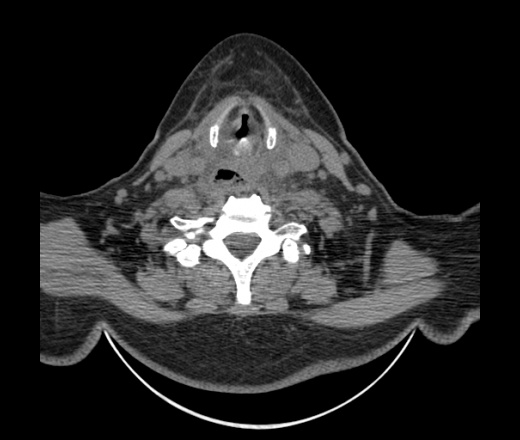

Женщина поступила в х/о спустя 4 дня после того как при употреблении карася подавилась костью.

Наличие газа в средостении на протяжении тел С2-С6 (медиастинальна эмфизема); рыбная кость на уровне тела С6.

При всем уважении, но говорить о медиастинальной эмфиземе, оценивая мягкие ткани шеи, как-то слишком резко. На мой взгляд, это ретрофарингеальное пространство.

Эвакуировали почти 100мл гноя. Но кость не смогли найти. Думаю что она даст дальнейшее ослоднение. Эндоскопически за черпалонадгортаной звязкой не смогли зайти в пищевод, все мягкие ткани отечные, просвет пищевода сдавлен. По всей видимости параэзофагеальная клетчака тоже задействована. Эмпиема, если ее можно так назвать, незнаю как правильно дошла до уровня яремной вырезки. Чем закончиться напишу. Ждем медиастинита.

Флегмона заглоточного пространства шеи, только операция, флегмоны вскрывают. Риск медиастинита.

Согласен с Вами; конечно, наличие газа в клетчатке ретрофарингеального пространства (затмение с опечаткой..). К сожалению, процесс "продвигается" к медиастиниту. Но почему никто, не отмечает наличие рыб. кости; или это для Всех очевидно?

Кость то мы сразу выявили, размеры где то 17*2мм, но ее так и не получается найти в этой каше